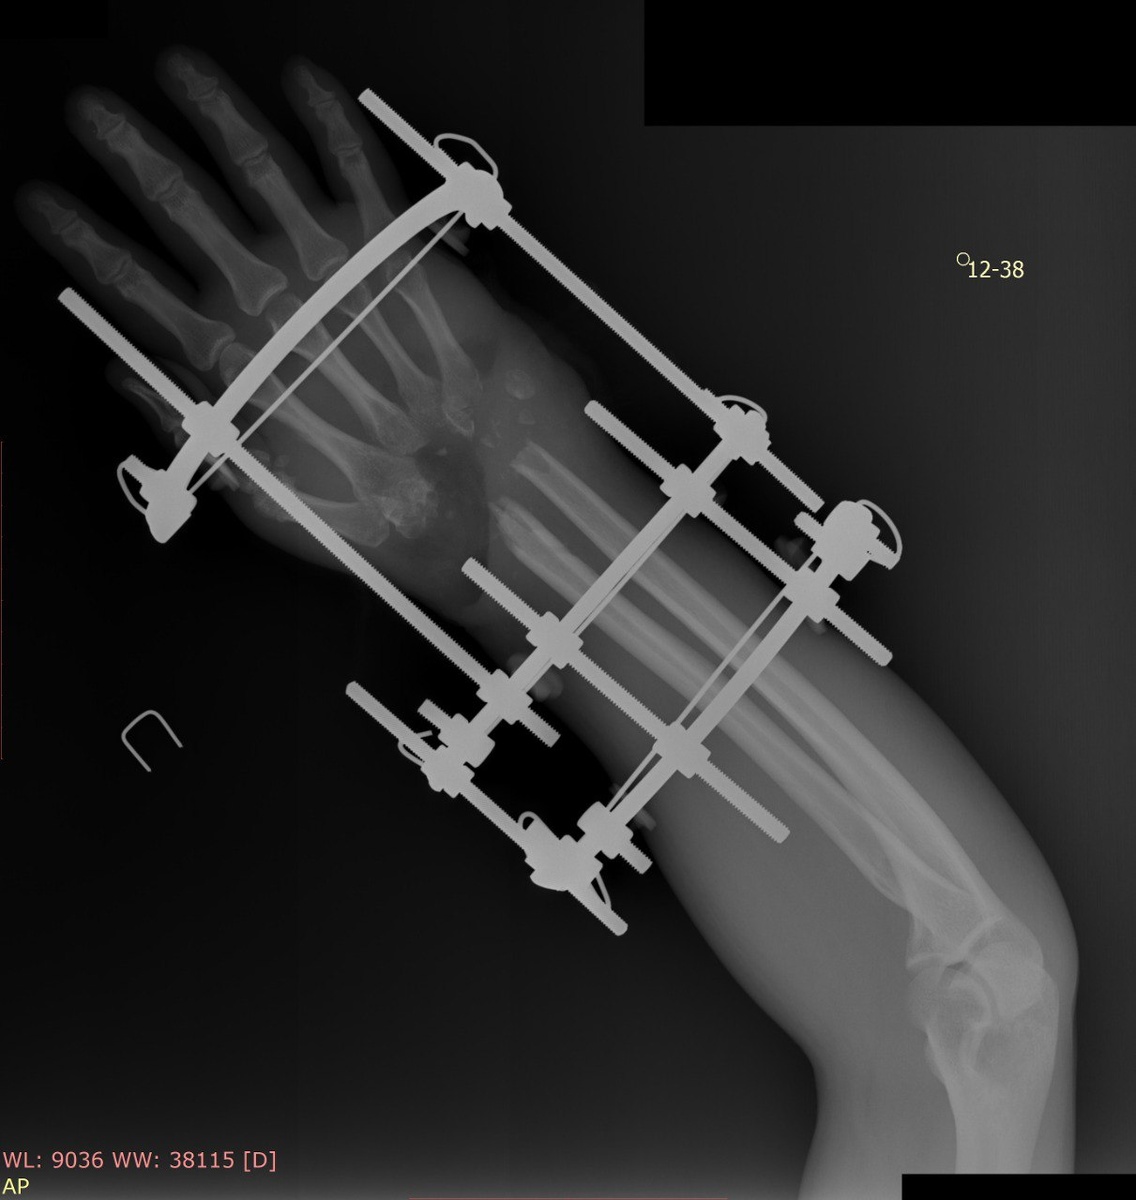

💥Сквозное осколочное ранение правого кистевого сустава с дефектом ВСЕХ 8️⃣костей запястья (ну ладно, немного приукрашено, кость-трапеция осталась, но от этого не легче), дефектом кожи, сухожилий разгибателей, дистальных концов костей предплечья. Ни с чем подобным мы ранее не сталкивались.🤷‍♂️

🥷Главной целью было победить инфекцию и стабилизировать кости. Если с первым пунктом более-менее понятно, то со вторым возникли вопросы. Было принято решение произвести артродез (замыкание) кистевого сустава с костной пластикой из гребня подвздошной кости. То есть срастить диафиз лучевой кости с аутотрансплантатом из таза, а его, в свою очередь, с основанием III пястной кости.

Дефект мягких тканей, который после радикальной хирургической обработки стал еще больше, заместили тыльным лоскутом предплечья. Последний представляет собой комплекс тканей, кровоснабжение которого осуществляется по отдельным сосудам. Донорское место закрыто 0,2 мм кожным трансплантатом с бедра.

Операцию закончили внешней фиксацией аппаратом, который фиксировал кости в правильном положении и позволял производить их взаимную компрессию весь период лечения. После того, как мы убедились в том, что артродез состоялся, аппарат демонтировали.